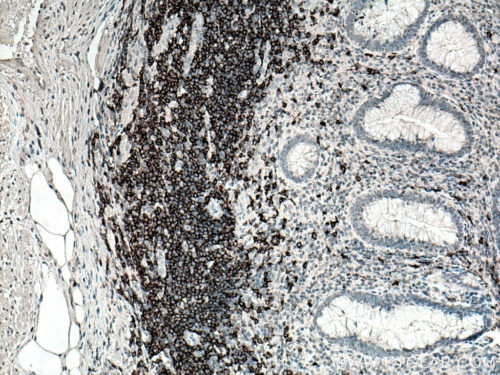

The two main types of lymphocytic leukemia are chronic lymphocytic (CLL) and acute lymphocytic (ALL). Patients have elevated levels of lymphoblasts (precursors of white cells) in their blood. These can be either T or B cell lineage. CD3 (Figure 1), CD4, and CD8, as classic markers of T cells, are a good prognostic marker of patient survival (PMID: 20846097). CD19 (Figure 2), an antigen widely present on B cells, persists in its expression on B cell-related cancer cells. It is often used in diagnosis (PMID: 8528044). Additional markers, namely CD20 (Figure 3), CD22, CD24, and CD79a, are used to study minimal residual disease – drug-resistant leukemic cells (PMID: 9492773). Plasma membrane staining of CD38 (Figure 4) and CD49d is often used in the clinic and their expression correlates with the disease severity and its response to chemotherapy (PMID: 10477712). ZAP70, an intracellular protein, is also a predictor of leukemia. It is involved in promoting prolonged signaling of the BCR pathway and the survival of cancer cells (PMID: 18577710).